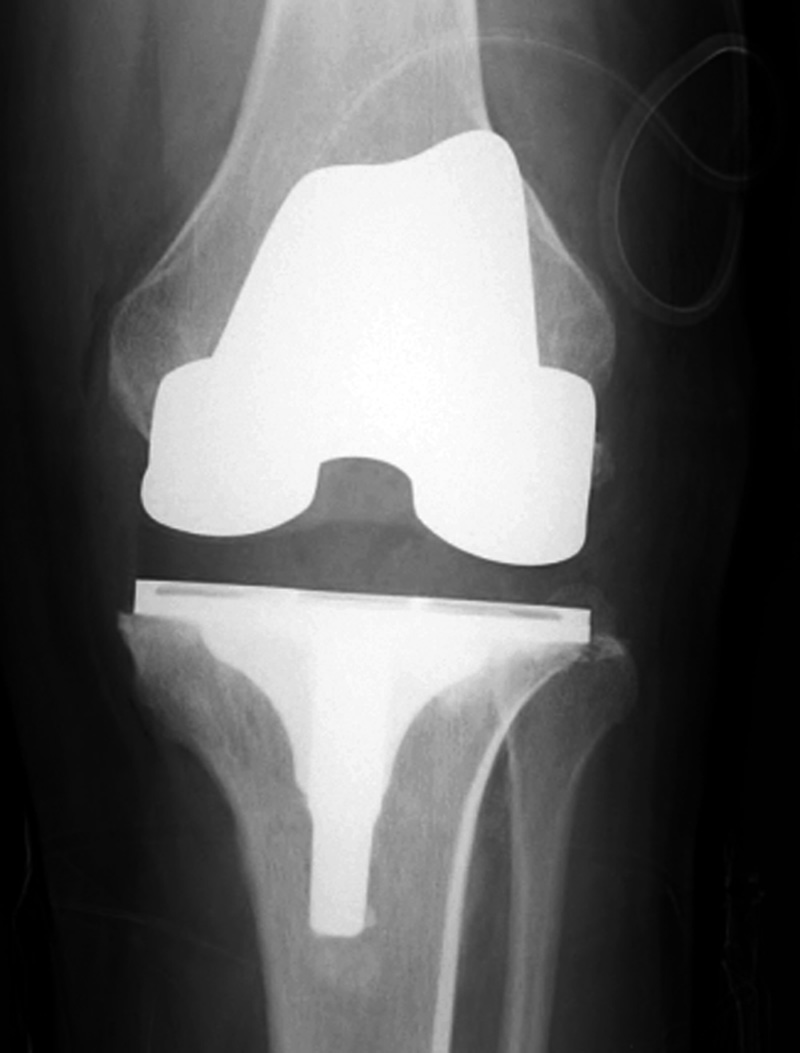

| Posterior cruciate retaining total knee arthroplasty (TKA) |

| Posterior cruciate retaining total knee prosthesis with cementless femoral and cemented tibial component and patellar resurfacing |